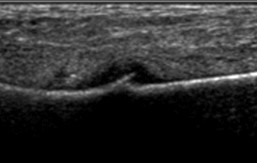

Mortonse Neuralgie is door de podoloog goed te diagnosticeren. De neuroom ( zenuwverdikking) is soms duidelijk zichtbaar tijdens ons echo-onderzoek. Compressie van alle middenvoetsbeentjes, het knijpen in de voorvoet zal de klachten provoceren. Vaak horen we bij het knijpen in de voorvoet ook een klik (Mulder’s Kliktest). Deze klik wordt veroorzaakt door het verspringen van het neuroom tussen de middenvoetsbeentjes van de derde en vierde teen.